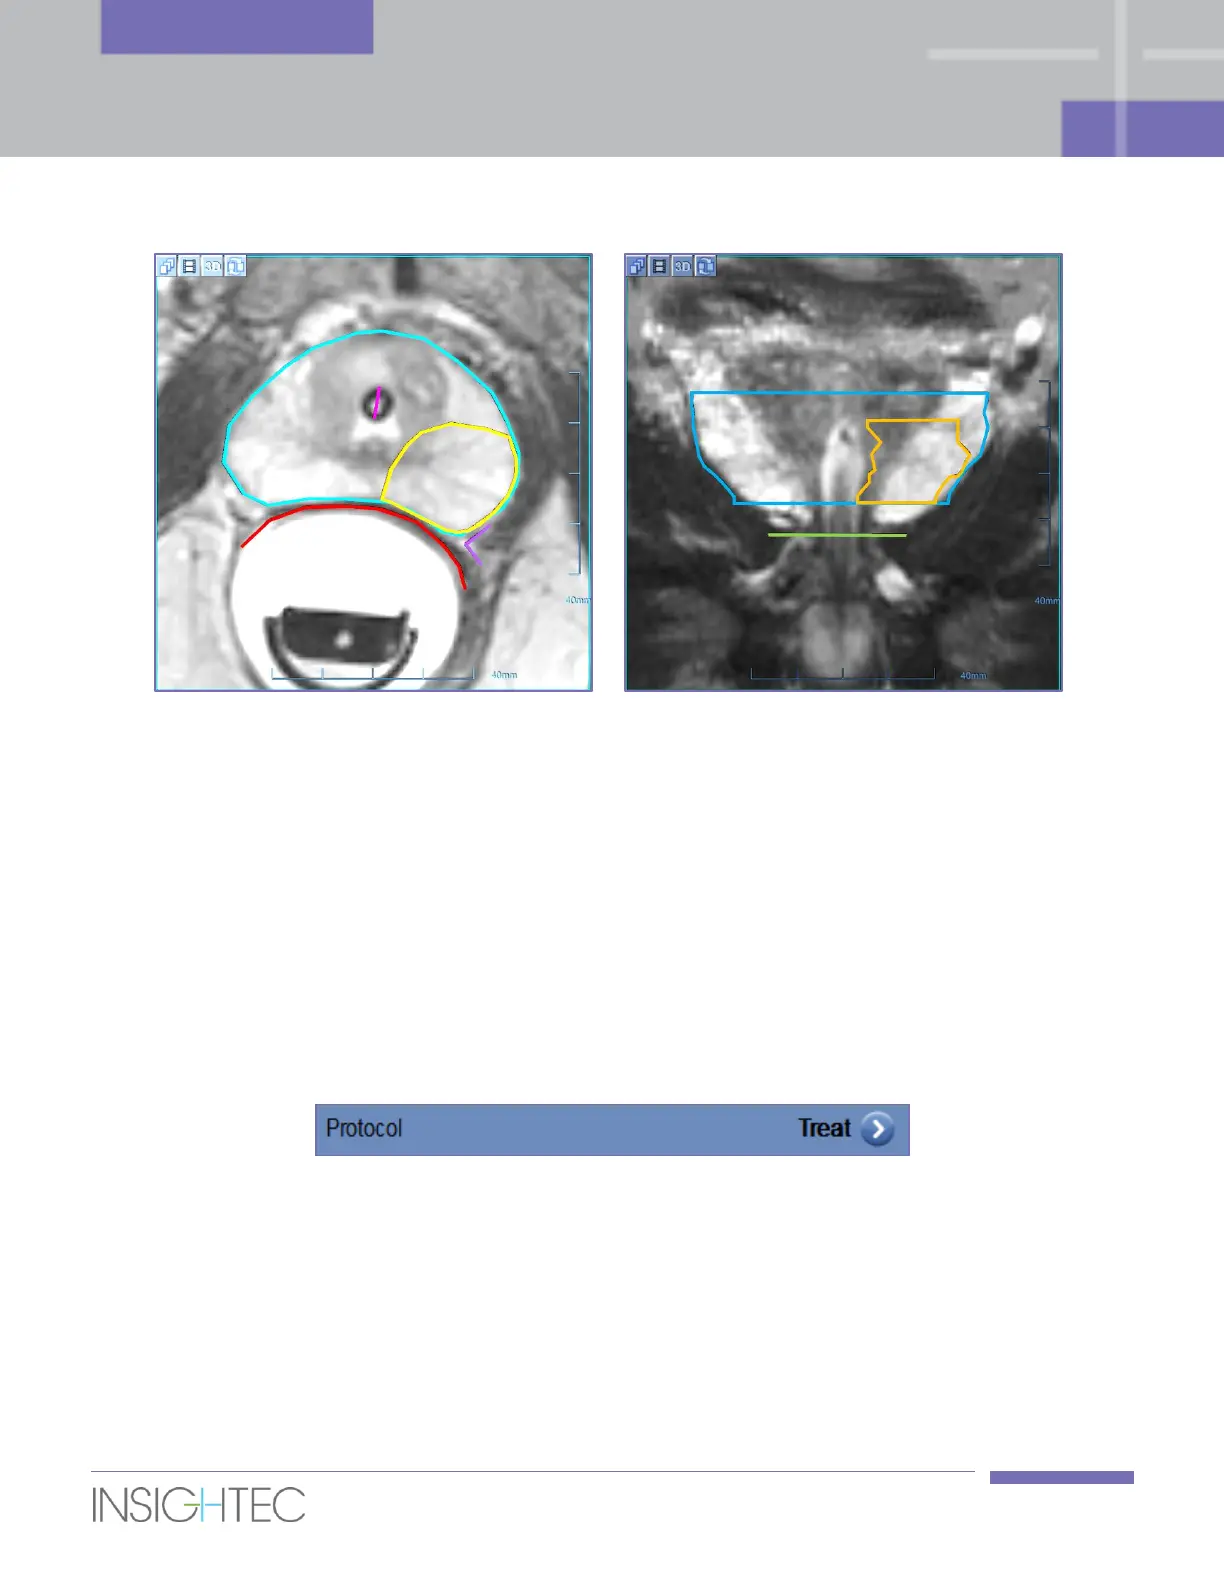

Figure 6-7: Planning images with drawing overlays (left Axial, right Coronal)